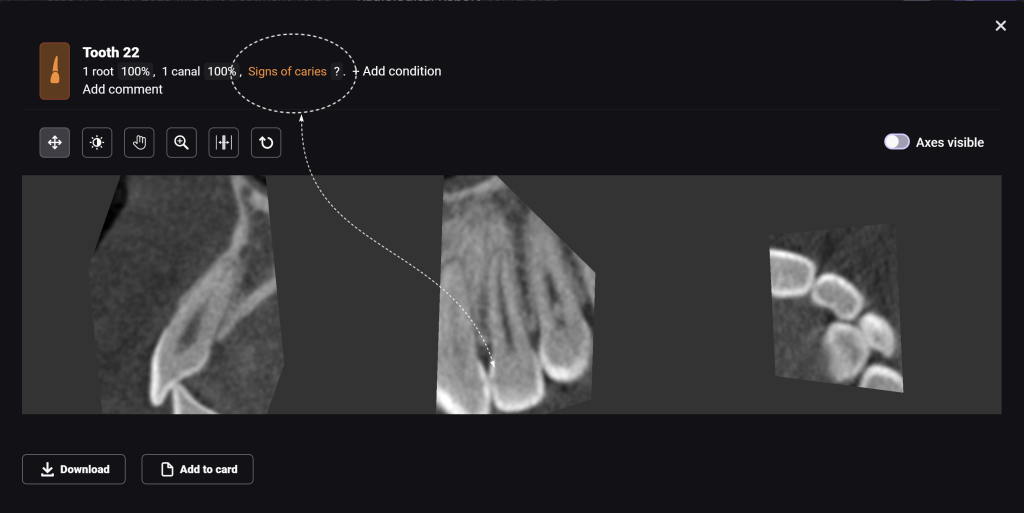

Diagnocat radiological report features an “Conditions with low probability” function. In this mode, teeth marked as “Low probability” are highlighted in yellow. Conditions such as caries and periapical lesions with a probability ranging from 30% to 50%

For example, in the area of tooth 22 (Universal 10), there is a label indicating “signs of caries.” However, they are poorly visualized at the CBCT

During the clinical examination, the presence of caries on the mesial surface of tooth 22 (Universal 10) has been confirmed